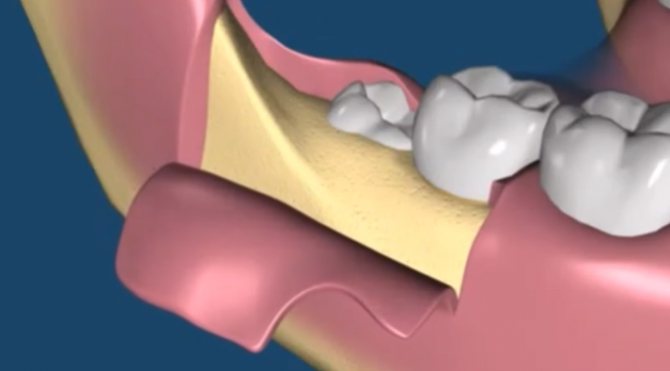

Несколько слов о процедуре

Удаление зубов – полноценное хирургическое вмешательство. Операция состоит из четырех этапов.

Как проводится эта методика – если лунка пустая, то под анестезией костные стенки лунки выскабливаются кюретажной ложкой, чтобы создать кровотечение и лунка заполнилась кровью (видео 3). Если же лунка заполнена грануляциями, то их тщательно выскабливают, т.е. делают тот же кюретаж (видео 4). Далее в обоих случаях после того как лунка заполняется кровью – в глубь лунки кладется противовоспалительное лекарство (Альвожель), а на слизистую накладывается несколько швов, чтобы сблизить края раны. Сразу же назначаются антибиотики.